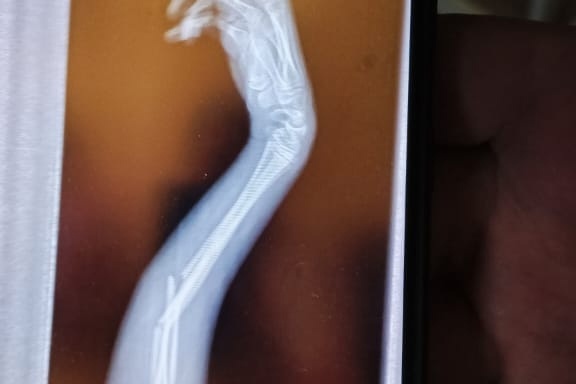

11-летний Андрей* сломал руку на уроке физкультуры. Инцидент произошел 7 апреля. Родители обратились в Коченевскую центральную районную больницу, где хирург наложил ребенку гипс. Тем не менее, сильные боли у мальчика не прекращаются – он принимает обезболивающие препараты.

Юлия Сергеевна добавила, что рука у ее сына болит все сильнее и сильнее. Из-за этой боли мальчик не может уснуть, а также испытывает проблемы с движением пальцами. Женщина предполагает, что рука «не полностью встала на место», что может привести к тому, что она неправильно срастется.